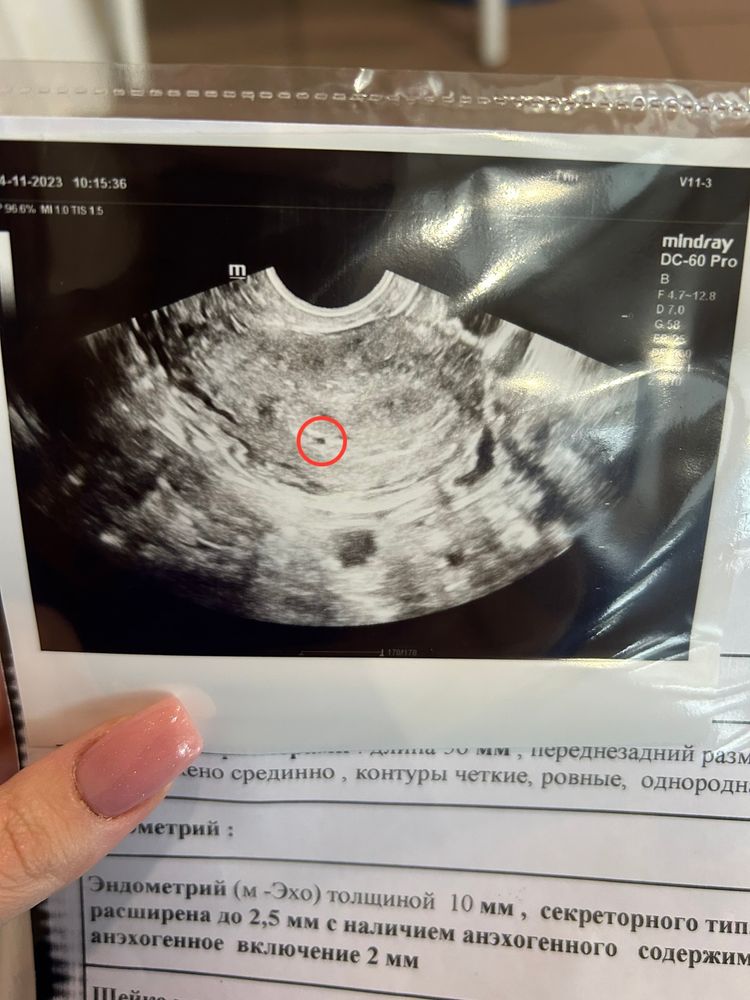

Узи в 4+6 недель

Приехала вчера в клинику на узи, а там плодное яйцо еле нашли, оно 2мм и в этом месте матка расширена на 2,5мм. Это не маловато?( у кого так же было??? Сейчас все хорошо у вас?